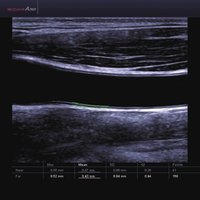

Das Samsung Accuvix A30 ist ein hochwertiges Ultraschallsystem, das mit seiner 3D-Technologie herausragende Ergebnisse ermöglicht. Das Sonographiegerät besitzt 5 Sondenanschlüsse und ist mit 20 unterschiedlichen Schallköpfen kompatibel. Mit dem A30 können Schallköpfe vom Typ Konvex, Mikrokonvex, 3D-Konvex, CW, Phased Array, Linear und Endokavitär verwendet werden. Bei zwei der Sonden handelt es sich um S-VUE Ultraschallsonden, die durch ihre höhere Bandbreite noch feinere Scans erzeugen.

Das Ultraschallsystem hebt sich besonders durch seine 3D-Technologie wie die Face Auto Detection für detaillierte Ultraschallbilder von Föten oder das Volume Shade Imaging, das sich auf die lebensnahe Darstellung von Schattierungen und Hauttönen fokussiert, ab. Mit weiteren wertvollen Technologien wie dem ElastoScan™ werden Tumore schneller erfasst und durch die HD Volumen Bildgebung sowie das DMR+™ eine erstklassige Bildqualität erzielt.

1 L4-7 Linear 4-7 MSK, Gefäße, Tiefe Venen

2 L5-13IS Linear 6-12 MSK, Weichteile, Gefäße, Brust

3 L5-13/50mm Linear 5-13 MSK, Weichteile, Gefäße

4 LS6-15 Linear 6-15 MSK, Weichteile, Gefäße

5 L7-16IS Linear 7-16 MSK, Weichteile, Gefäße, weibliche Brust, Pädiatrie, Oberfläche